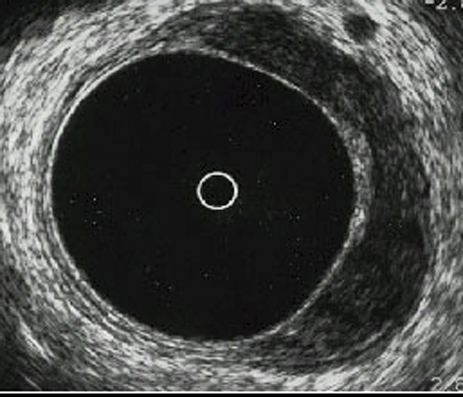

Ecografía rectal uT3 N+